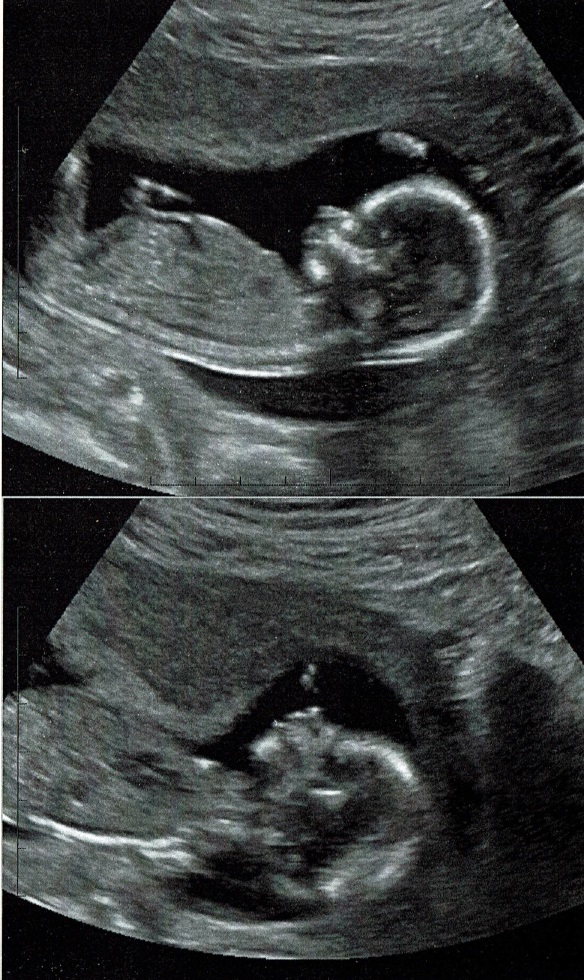

These were taken at 15 weeks. Any guesses? Attachment 42704

I feel the nub is mostly cutoff but I'll give a very tentative pink lean.